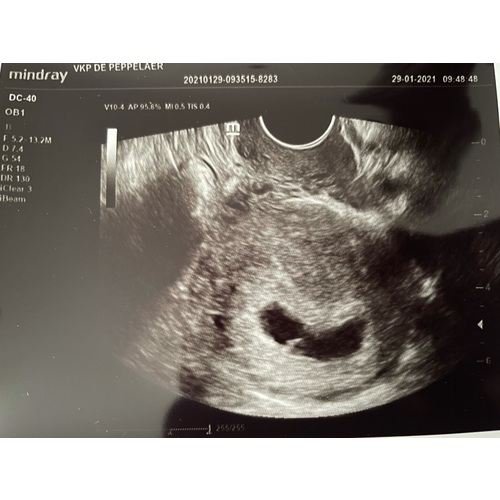

Dit was bij 6-7w